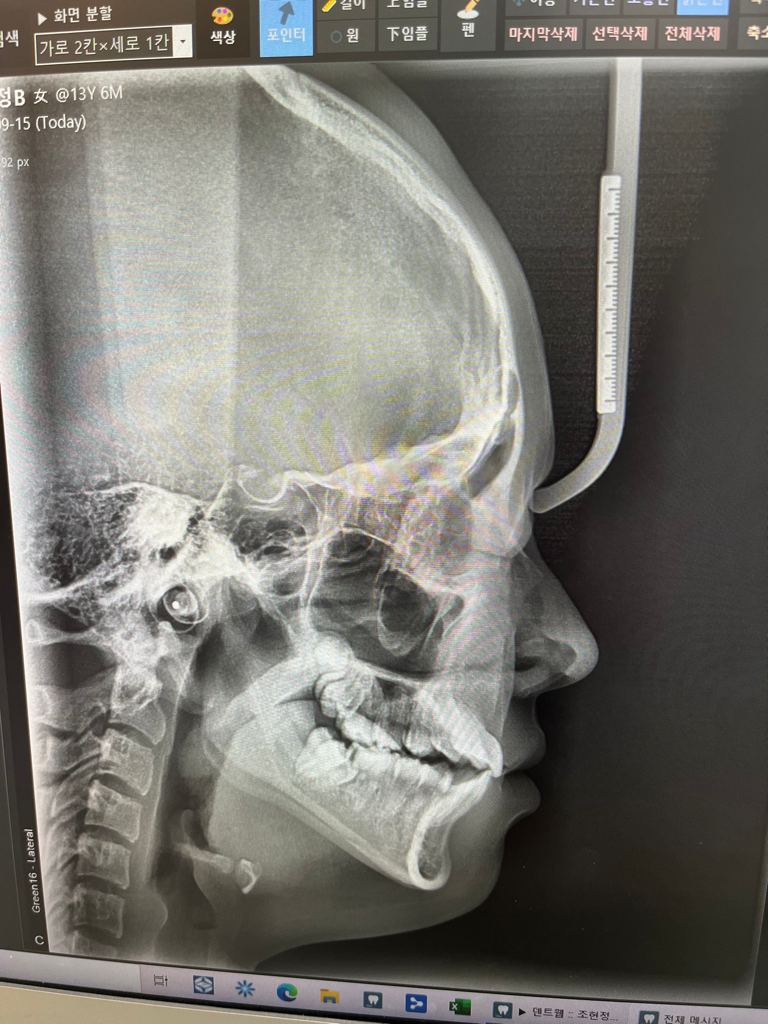

중1딸아이 치아엑스레인데 전체교정 필요할까요??

전 어금니 누운것만 하고싶은데

• 1번 째 사진

엑스레이만 가지고는 사실 교정 진단을 하기는 힘듭니다만 간단히 봤을 때에는 전체 교정이 필요해 보입니다.

정확한 분석을 위해서는 좀더 진단이 필요하지만 올린 x ray 사진만 보아도 전체 교정을 해야 할 것으로 보이며 부분교정은 아무 드물게 사용합니다.

누워잇는 치아를 끌어 올리기 위해서는 공간확보가 필요한데 아마 전체 교정을 해야될 가능성이 높아 보입니다. 교정 진단을 해봐야 알겟지만, 단순히 저 치아만 올리는건 쉽지 않아 보이네요.